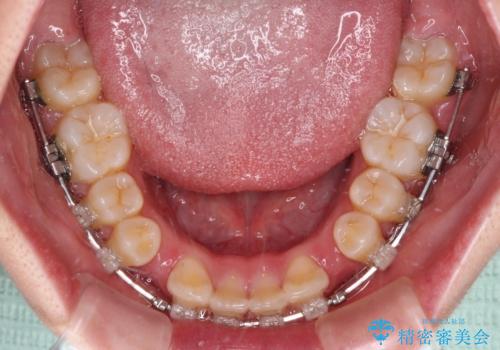

前歯が2本ない ワイヤー装置での抜歯矯正

- 矯正装置

- クリアブラケット

- 下顎前歯欠損による隙間と、上顎前歯の突出感を気にして来院された患者様です。

横顔に出っ歯の印象はありませんでしたが、下顎のスペースと上下前歯の前後位置の大きなズレを改善するために、上顎左右の第一小臼歯2本を抜歯しすることとしました。

口元が引っ込みすぎないようにするために、上下ともに臼歯を前方に移動させる必要があり、インビザラインでは対応できないため、表側のワイヤー装置にて矯正治療を行うこととしました。